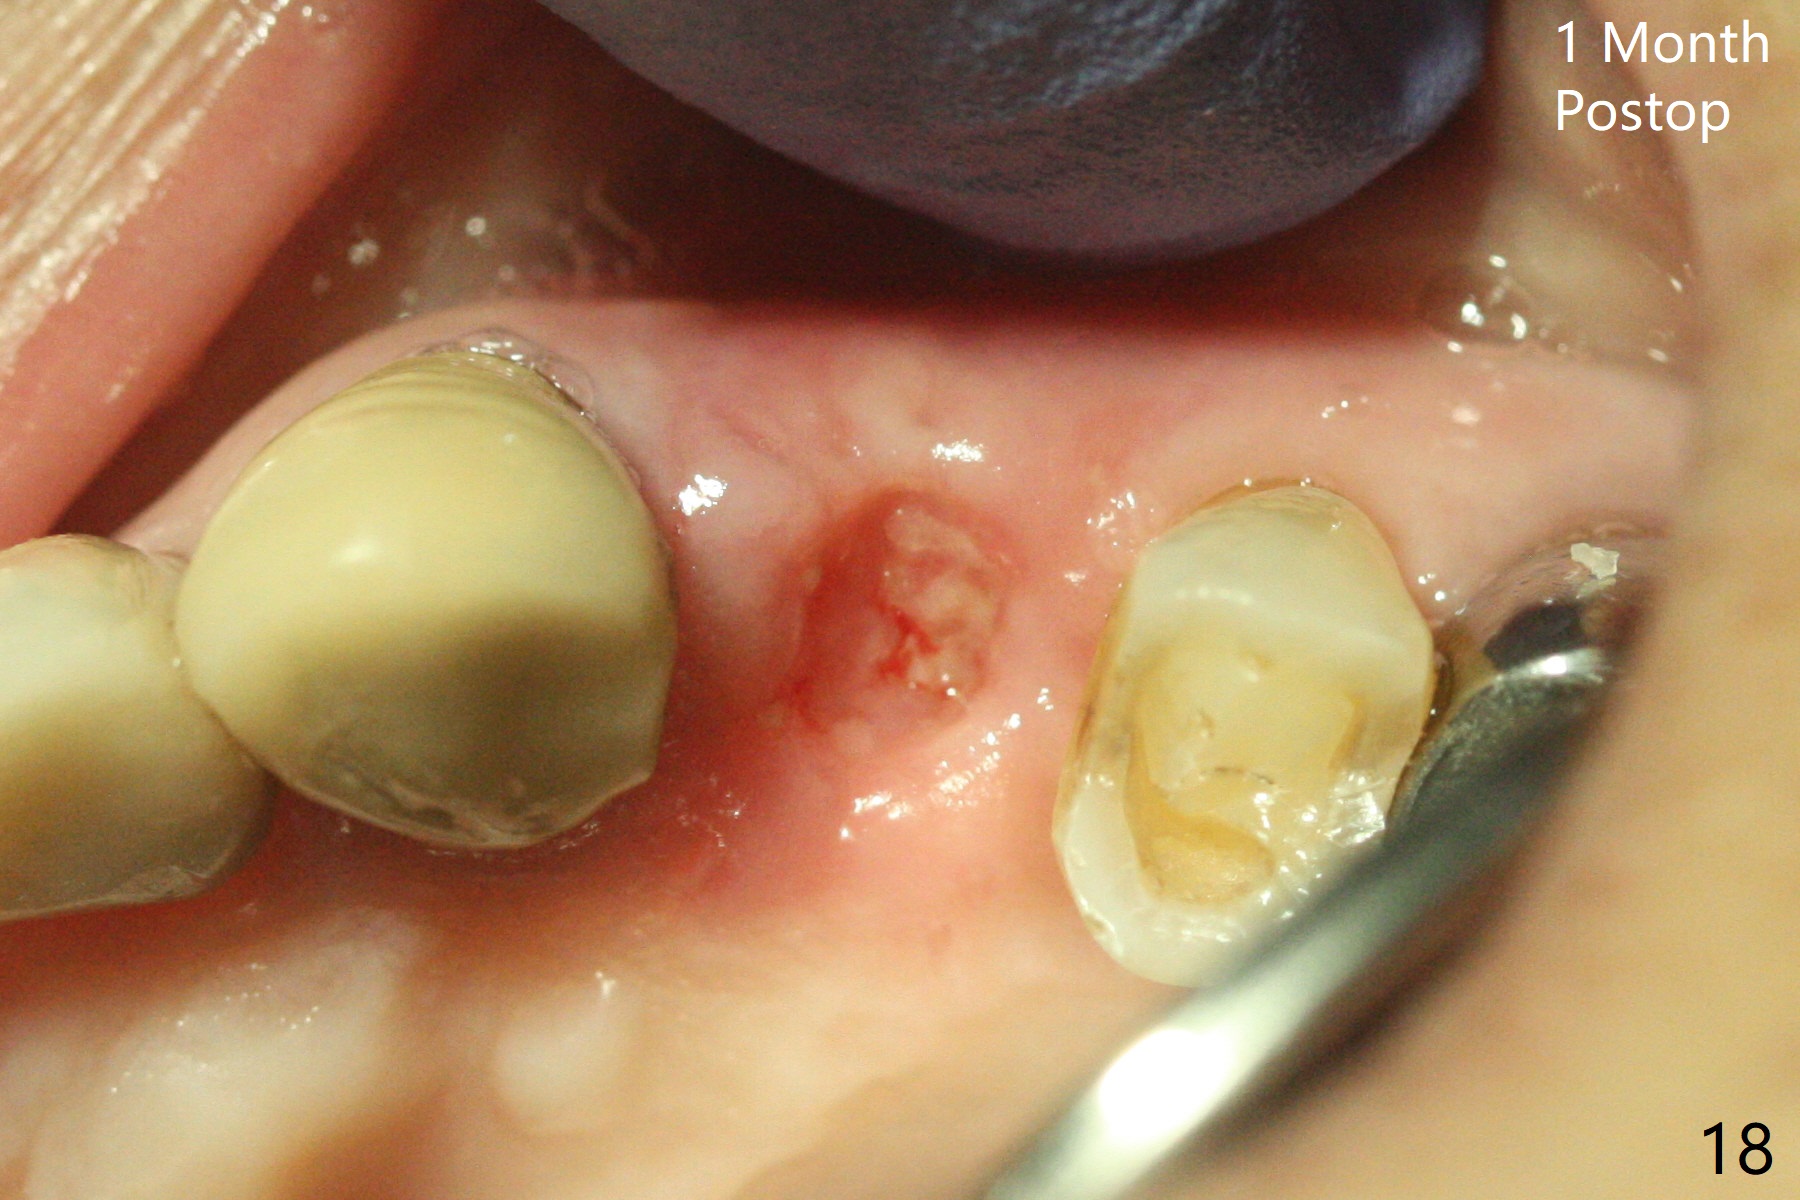

68岁女左上4颊侧瘘道(图一:*),与根尖颊侧骨板缺失相通,其实腭侧根尖周围病变更大(也与颊侧窝相通),术中没有注意腭侧根接近3(图二:P),稀里糊涂的基本顺着腭侧根(颊侧)走向钻洞(图四,与图三理想方向对比),突然记起术前设计钻洞必须在腭侧牙槽窝远中颊侧,在远中建立新洞眼(图五),之后无法再次建立新洞眼,只好利用同一个侧面切割钻头将钻洞往远中移位,同样效果不佳(图六),最后只好放弃,放置粘性骨粉(图七:*),覆盖PRF膜,6个月胶原膜,PGA缝线,牙周胶水。术后重新分析表明顺着腭侧牙槽窝种植与尖牙还是有分离(图八,九:*),因为牙槽窝是斜型的(图十:黑色),不过离颊侧骨板也接近(图八:B)。所以钻洞必须斜型针对远中骨壁,表浅些(图十一:红色箭头);一旦进入骨板,改变角度(图十二:红色箭头),适当矫枉过正,随着植体增大,钻洞会往近中偏移(白色箭头)。最好植体方向理想(图十三)。不过植骨后钻洞偏移可能性比较少。缝线和牙周胶水似乎是一个稳妥固定胶原膜方法。术后病人抱怨水肿严重,术后八天颊侧根尖隆起是由于骨粉推出骨板之外(图十五,十六:*),上颌窦底板无意穿孔(^)伴有上颌窦膜(M)增厚,与术前对比(图十七:上颌窦窦腔清晰)。术后一个月6个月吸收膜不见了,大多数缝线已经脱落,最后两根缝线撤除后,牙槽窝开口已经关闭,好像主要成分是骨粉(图十八)。术后5个月牙槽嵴宽,角化龈也宽,好像可以植入4x11.5毫米植体(图十九)。